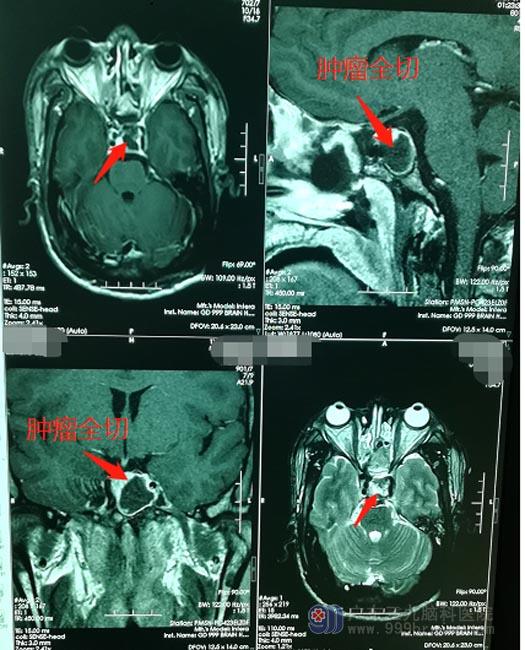

裴先生和家人商量后,一致同意手术治疗。鲁明带领神经外五科手术团队为裴先生实施了“内镜下经鼻蝶侵袭性垂体瘤占位切除术”,术中将肿瘤全切。术后未出现脑脊液漏;病理检查结果:(鞍区)密颗粒型生长激素细胞腺瘤。现在,裴先生已顺利康复出院。